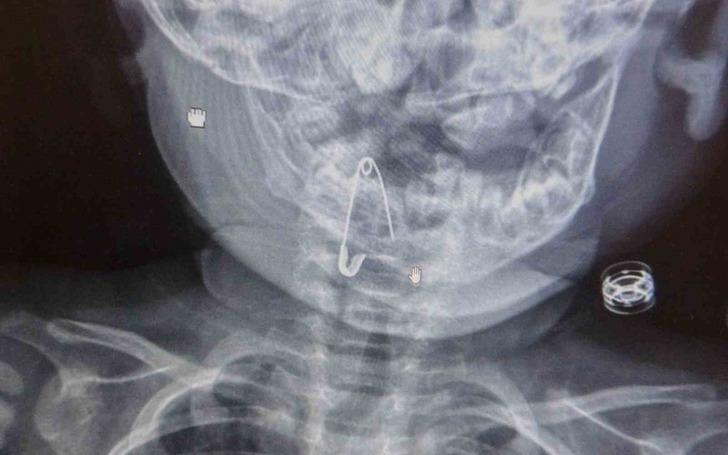

Güroymak ilçesinde 8 aylık bebek, evde bulunan çengelli iğneyle oynarken onu yuttu. Öksürmeye başlayan minik çocuğun, hastanede çekilen röntgen sonucu çengelli iğneyi yuttuğu fark edildi.

Konuyla ilgili açıklamada bulunan Kulak Burun Boğaz Hastalıkları Uzmanı Operatör Dr. Hakan Tuhan, “8 aylık bir bebek, Bitlis’in Güroymak ilçesinden tarafımıza danışıldı. Güroymak ilçesinde çekilen röntgen sonucunda çengelli iğnenin soluk borusunun girişinde olduğunu teyit ettik. Yapılan müdahaleler sonucunda çengelli iğneyi çıkardık. Çıkardıktan sonra iki saat kadar gözlem altında tuttuk hastamızı. Daha sonrasında herhangi bir komplikasyonla karşılaşmadık ve sorunsuz bir şekilde taburcu ettik” dedi.